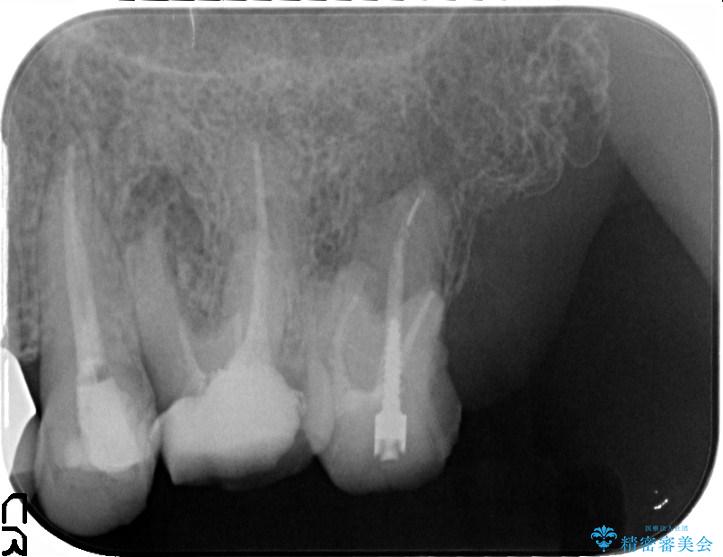

クラウンが装着されておらず、つぎはぎだらけの処置歯を、精度の高いセラミッククラウンを用いて歯ブラシのしやすい環境整備を行っていきます。

セラミッククラウンの治療は、天然の歯のような審美性を回復できることも大切ですが、精度が高くきっちりと歯ブラシを行いやすい状態を整えることで虫歯や歯周病の再発リスクを下げることも非常に大切です。